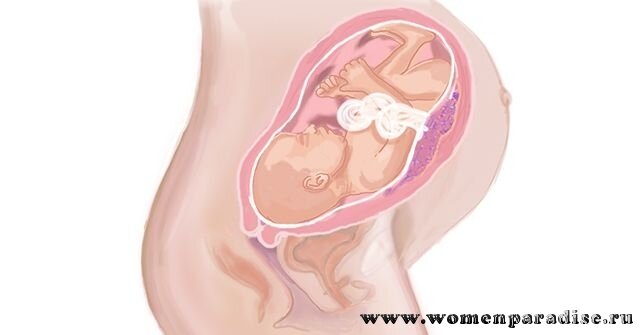

Тошнота на 37 неделе беременности: причины и рекомендации